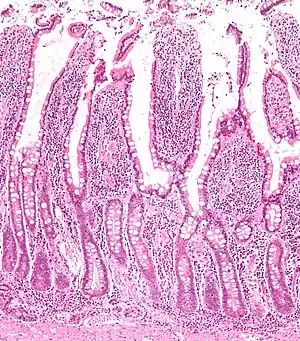

为了使消化物中的营养尽可能地被充分吸收,小肠通过环状襞(拉丁語:)、微绒毛与肠绒毛结构使其内表面面积得到了极大的扩增。环状襞使内表面面积扩大了3倍,肠绒毛使其又扩张了7到14倍,微绒毛使其扩张了15到40倍,绒毛内有丰富的毛细血管、毛细淋巴管。在肠绒毛之间还存在着肠腺(拉丁語:),使得内表面面积可以得到进一步的扩增。这些结构带来的表面积扩张使用于营养物质重吸收的小肠部分内表面面积最终可以达到200m²[4]。

经过消化的食物现在可以透过肠壁通过扩散作用进入血液,大部分营养物质都将在小肠中得到吸收。小肠的粘膜上排列着简单的柱状表皮细胞,并被名叫环状襞的结构覆盖。与褶皱结构不同的是,环状襞被认为是可以永久性进行延展和伸缩的结构,而褶皱则不是永久性的。通过显微镜可以观察到环状襞含有类似于手指形状的绒毛结构(拉丁語:),而就单独的表皮细胞而言其又含有类似手指形状的微绒毛结构。环状襞、绒毛与微绒毛的作用是用于扩大小肠内表面积,并给营养吸收提供足够的空间。